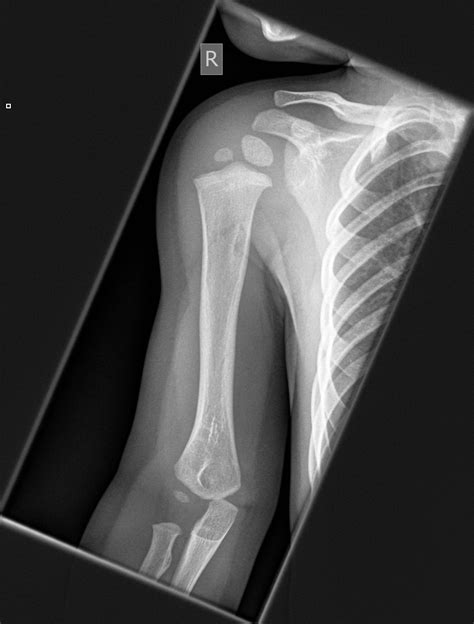

Interpreting a normal Xray of shoulder involves understanding the key anatomical structures visible in the images. A normal shoulder X-ray should show:

• Clear and distinct outlines of the humerus, scapula, and clavicle.

• Normal joint spaces without signs of narrowing or erosion.

• No evidence of fractures, dislocations, or bone spurs.

• Symmetrical appearance compared to the contralateral shoulder.

Here is a table outlining the key structures visible in a normal shoulder X-ray:

Structure Description

Humerus The long bone of the upper arm, which articulates with the scapula to form the shoulder joint.

Scapula The shoulder blade, which provides attachment points for muscles and ligaments.

Clavicle The collarbone, which connects the shoulder to the sternum.

Glenoid Fossa The socket of the scapula that articulates with the humeral head.

Acromion The bony process of the scapula that forms the highest point of the shoulder.